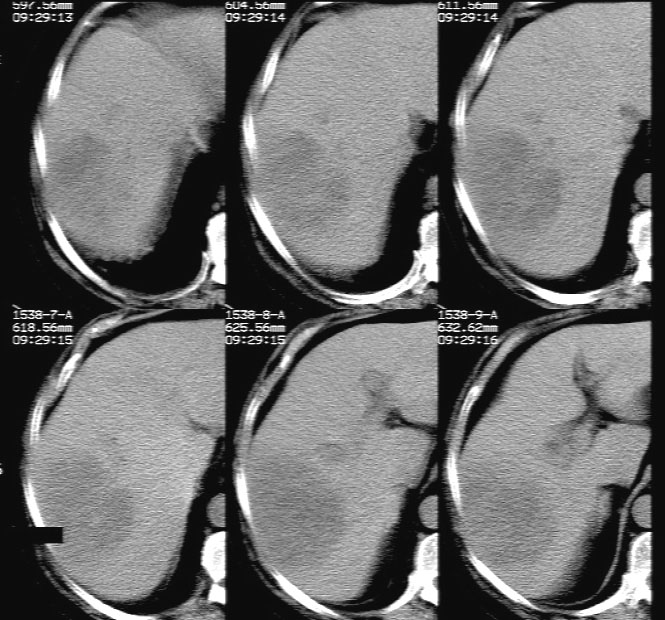

平扫示: 肝右后叶见团状低密度灶,边界欠清,密度略不均匀,ct值28-32hu,肝内胆管无扩张。

ct增强扫描示: 动脉期肝右后叶团状低密度边缘明显不均性强化,内呈不规则峰窝状低密度(无强化区),不规则分隔亦见明显强化;三期扫描像均见,病灶有明显占位征,周围血管、胆管推挤外移,病灶与正常肝组织分界不清,延迟期病灶周围见雾状略低密度(较肝左叶)。